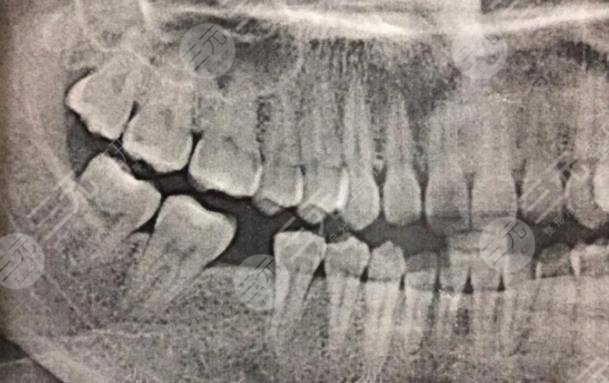

我的牙齿有一颗牙齿坏了很久了,所以我一直想要修复,但是我又不想拔掉,所以就很纠结,不知道怎么样的方式才能够改良,经过朋友的一番介绍说,我还是选择到口腔医院里面检查一番,然后再决定具体的缓解方法。在和口腔医院的医生沟通之后,他说像我这种方情况必须要把原有的坏牙拔掉之后换新的牙齿,不会有口腔造成疾病的情况。

在听了医生的介绍之后,我决定选择使用这种方法,没想到这种方法确实GET了不错的目的,现在我种植牙齿之后已经有快两年的时间了,没有出现任何的副作用,平时也没有出现牙齿疼痛的现象。